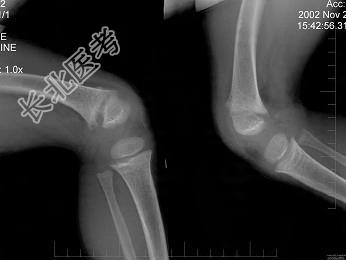

- 单项选择题男,6岁, 睡眠差,夜惊, 多汗;出牙较迟; 血清磷减低、血清钙减低、碱性磷酸酶升高,请结合图像选择最佳选项  (    )

A、维生素D缺乏病

B、骨软化症

C、先天性骨梅毒

D、肾性维生素D缺乏病

E、脆骨病